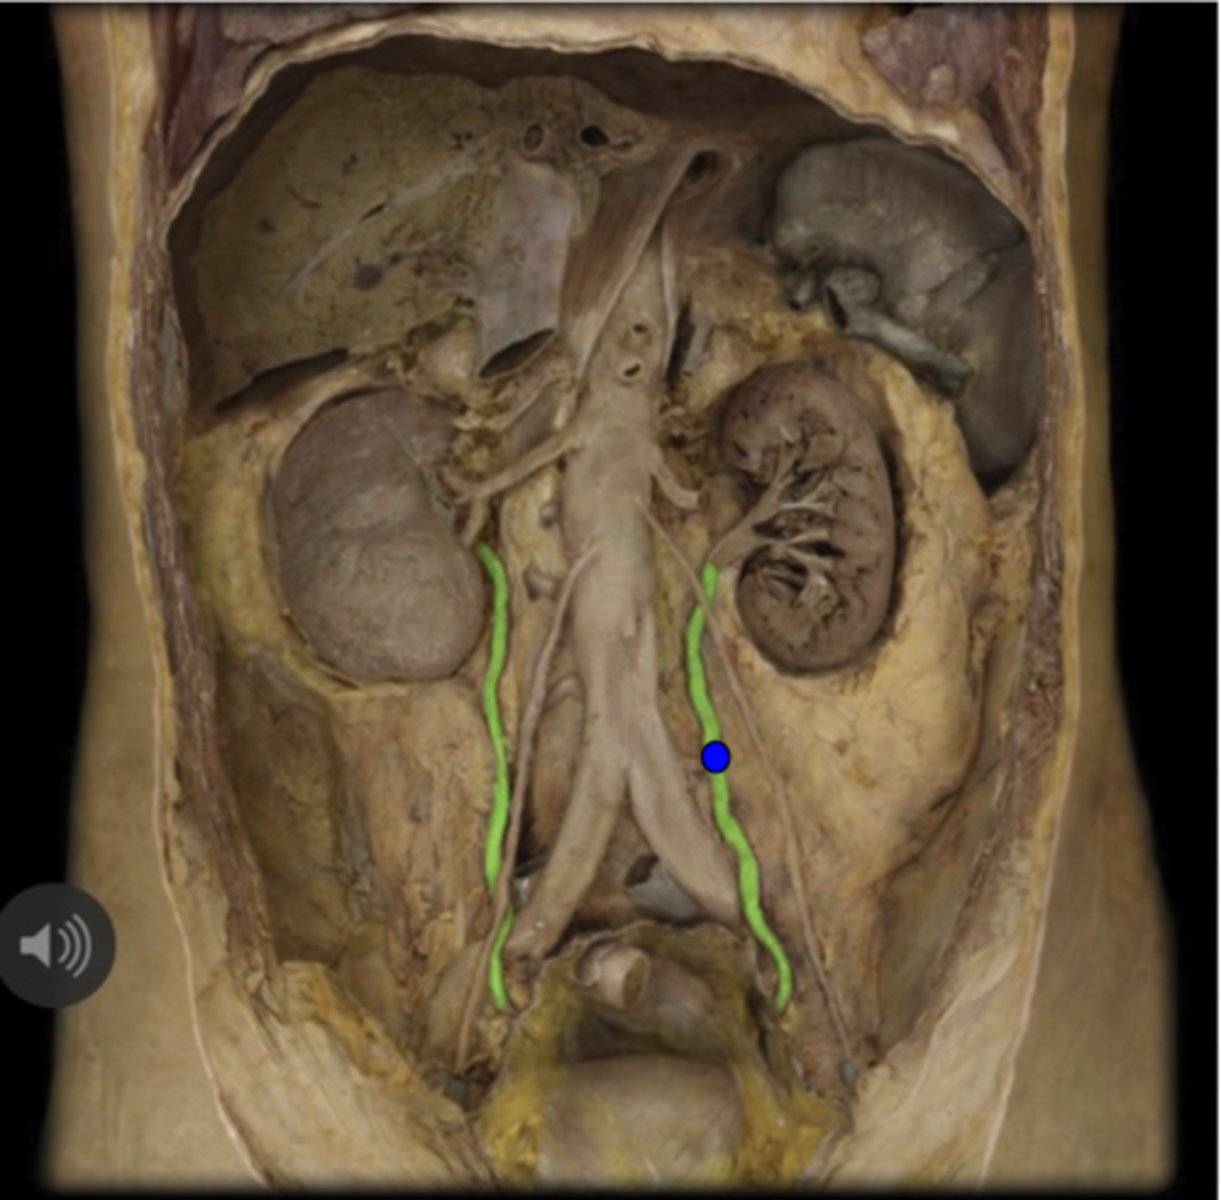

Right Ureter

Left Ureter